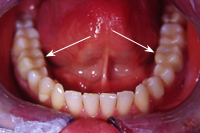

Nach Erreichen dieser Ziele hat Vanessa die beiden "Stummel" in einer vierstündigen "Übung" mit viel Geduld und grossem handwerklichen Können mit Kompositfüllungen zu perfekten, absolut kaustabilen Zähnen rekonstruiert (Abb. 2).